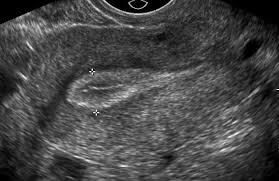

A pelvic ultrasound is a test that uses sound waves to make pictures of the organs inside your pelvis. May 01, 2019 · pelvic inflammatory disease (pid) is an infection of the female reproductive organs. Such cases of bilateral pelvic kidneys can cause serious difficulty in normal delivery/ childbirth. A test in which sound wave are used to examine internal structures. The pelvis is in the lower abdomen and includes the fallopian tubes , ovaries , cervix , and the uterus. In this female patient, ultrasound images show an incidental finding, which is rather rare. A pelvic ultrasound allows quick visualization of the female pelvic organs and structures including the uterus, cervix, vagina, fallopian tubes and ovaries. A pelvic ultrasound is a noninvasive diagnostic exam that produces images that are used to assess organs and structures within the female pelvis.

In this female patient, ultrasound images show an incidental finding, which is rather rare. Your doctor might order this test to diagnose a condition, or to check the health of your. A pelvic ultrasound is a test that uses sound waves to make pictures of the organs inside your pelvis. During pregnancy, it can be used to examine the fetus. Many of our female patients come to us with concerns about pain after a hysterectomy.